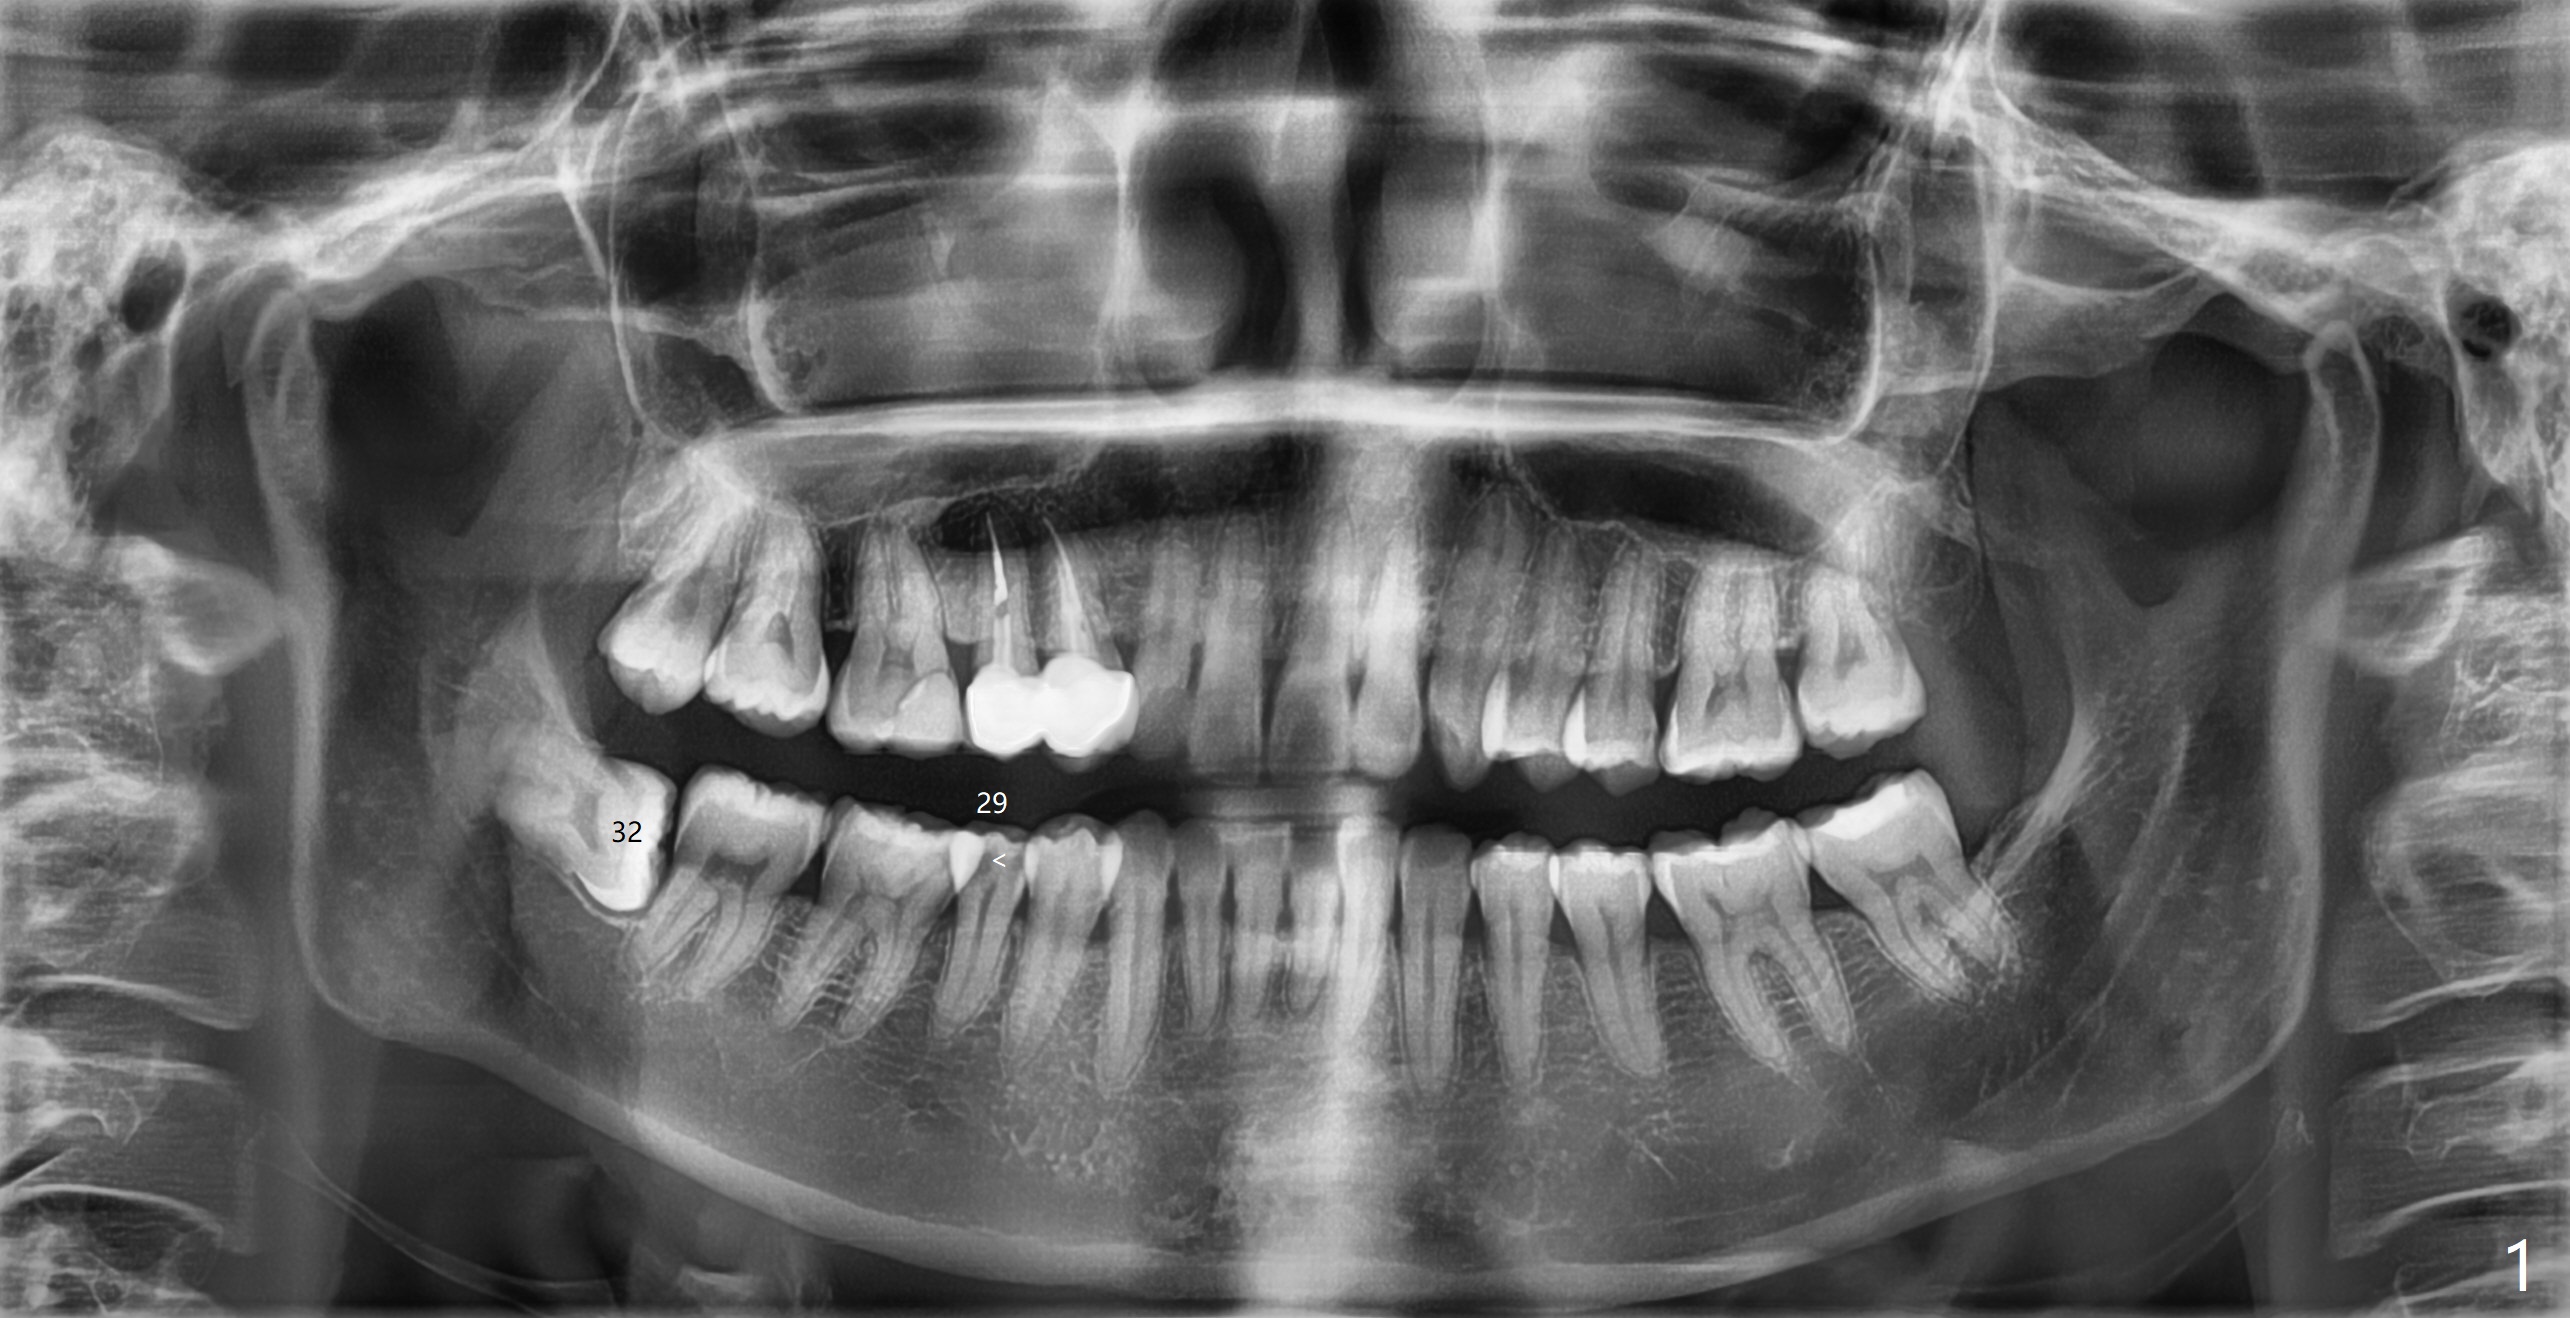

A 36-year-old nervous woman with left TMJ click agrees to have #29 with caries (<) and 32 extracted in preparation for orthodontic treatment (crowding, Fig.1). With 1/2 of Collagen plug placed in the apical portion of the socket, Bond Apatite (1 cc, A) is placed, followed by the other 1/2 of Collagen Plug coronally (Fig.2). Sutures are removed 22 days postop; the wound heals.